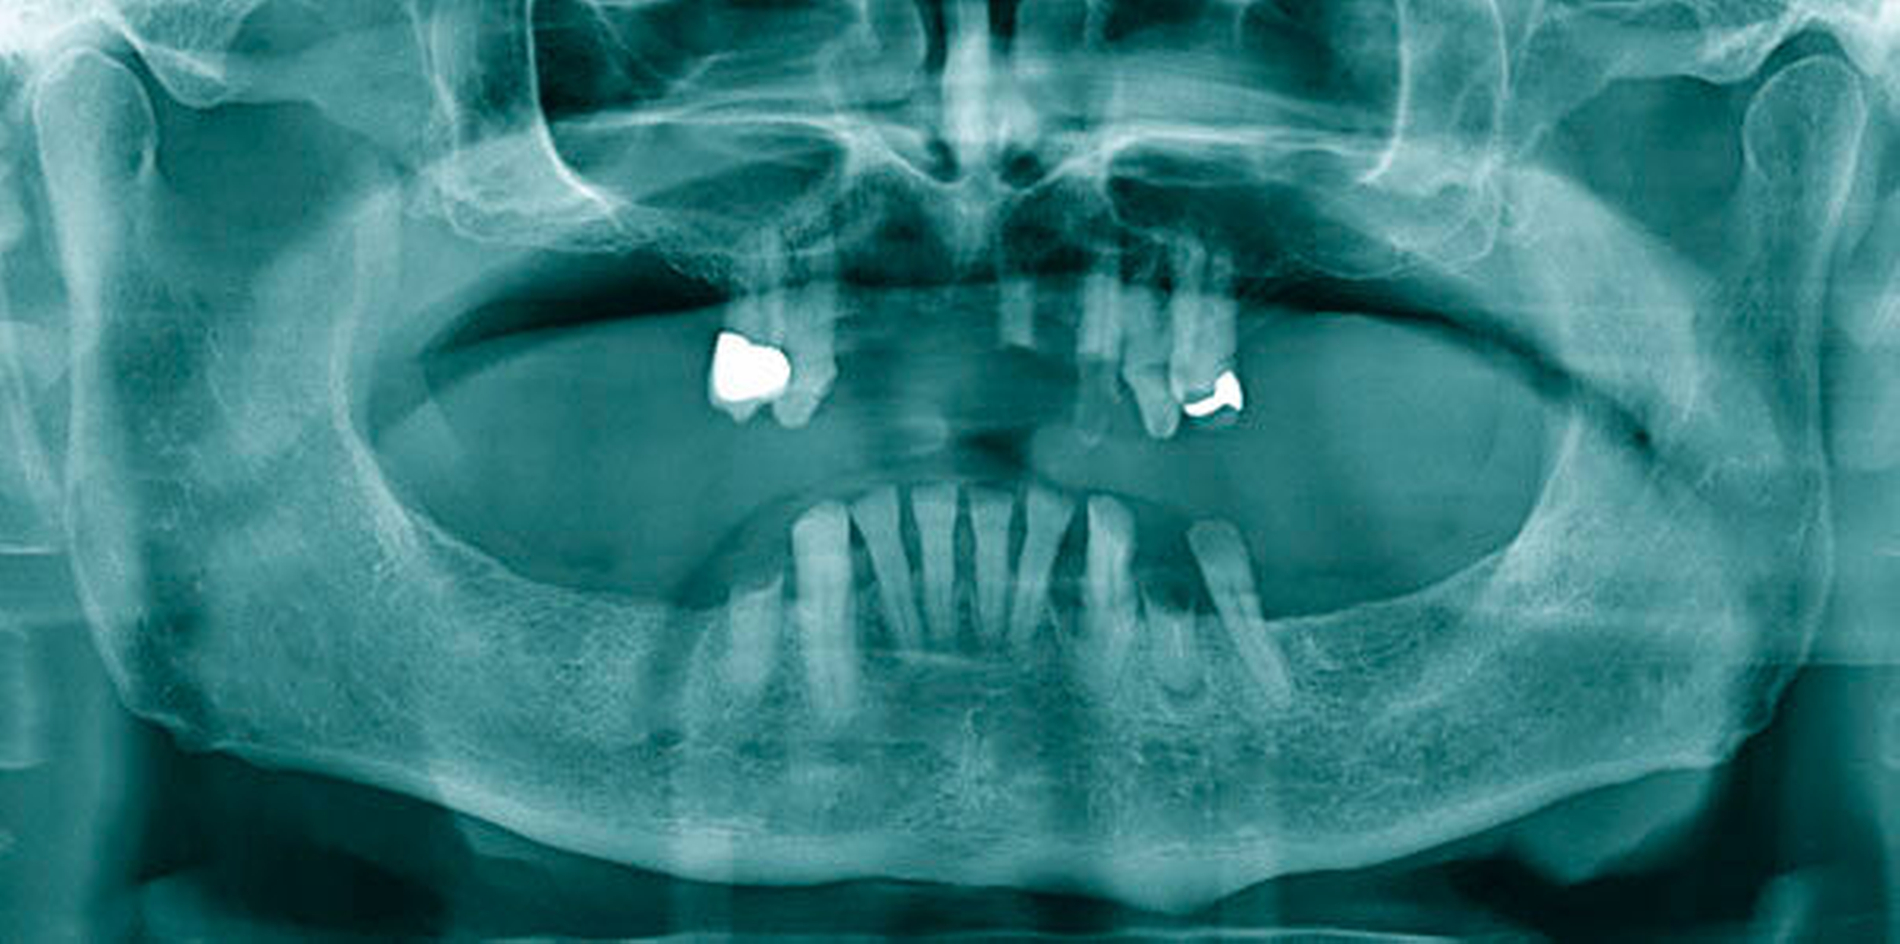

Abbildung 1 A-I: 84-jähriger Patient mit arterieller Verschlusskrankheit (Claudicatio intermittens)

Senioren haben – wie oben ausgeführt – immer häufiger zahlreiche eigene Zähne. Im Fall von Lückenbildungen müssen diverse Behandlungsalternativen in Erwägung gezogen werden. Dazu zählen neben klassischen prothetischen und implantologischen Versorgungen auch andere Optionen (Tabelle 1). Nicht jede Lücke muss geschlossen werden. Wenn funktionell und ästhetisch keine relevanten Einschränkungen bestehen, kann auch ein Monitoring (Belassen und Beobachten) eine gute Lösung sein [Staehle, 2010; Listl et al., 2016]. Daneben kommen zuweilen Zahnumformungen und -verbreiterungen (Abbildung 1) oder direkte Freiendanhänger aus Komposit als Behandlungsmittel zum Lückenschluss in Betracht [Staehle, 2007, 2009, 2010, 2012, 2017; Staehle et al., 2014, 2015a, b; Frese und Staehle, 2018]. Schließlich ist für Patienten, bei denen aufwendiger festsitzender Zahnersatz nicht möglich ist und die keine herausnehmbare prothetische Versorgung wünschen, die Verfolgung des Prinzips der verkürzten Zahnreihe [Walter, 2016] zuweilen eine gute Alternative. Zur praktischen Realisierung dieses Konzepts kann heute die konservierend-restaurative Zahnheilkunde (zum Beispiel über Zahnverbreiterungen und -anhänger, eventuell in Kombination mit Schienungen) ebenfalls viel beitragen.